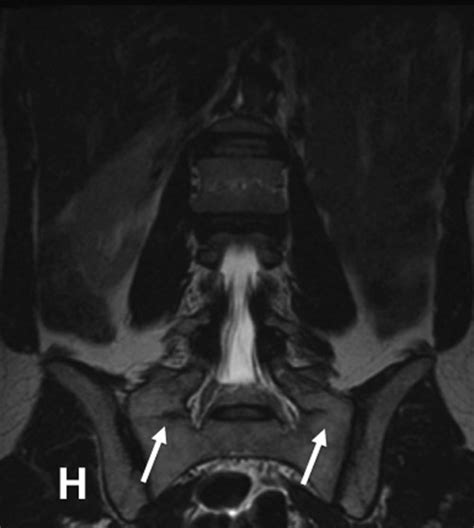

Accurate diagnosis of conditions affecting the lumbosacral transitional segment is essential for effective treatment. Several diagnostic methods are commonly used to evaluate this region:

• Imaging Studies: Imaging techniques such as X-rays, MRI, and CT scans are crucial for visualizing the anatomy of the lumbosacral region. These studies can reveal degenerative changes, herniated discs, spinal stenosis, and other abnormalities.